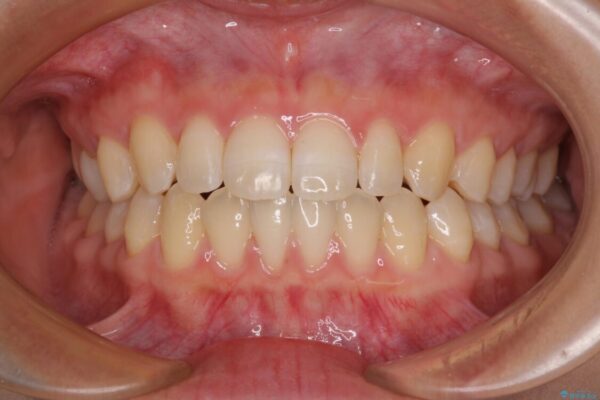

前歯の上下スペースと前歯の隙間を気にして来院された患者様です。

飲み込みや話をするときに舌を突出させる癖が強くあり、それが原因でスペースが空いていました。

舌癖を改善するためのトレーニングを行いながら、インビザラインにより上下の前歯の隙間を閉じていくこととしました。

治療後

• 隙間だらけの歯列 インビザラインで改善 治療後画像